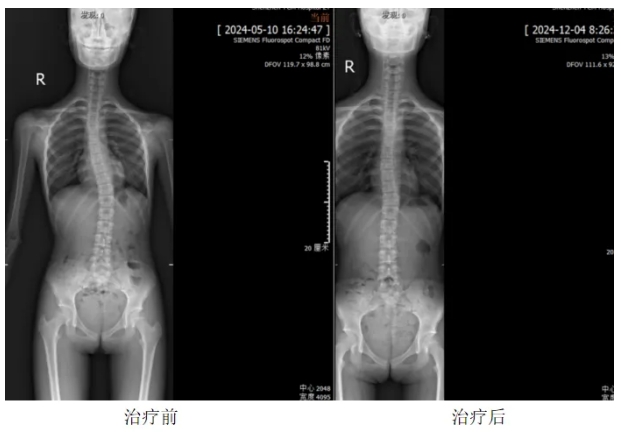

本次训练营采用中华中医药学会整脊分会主任委员、深圳市中医院推拿(整脊)科学术带头人林远方教授独创的1+X特色矫正训练模式,结合国际最新脊柱矫正技术,个性化定制每位孩子的训练计划。通过“理筋、正骨调曲、练功”三步法,帮助孩子有效改善脊柱侧弯,重塑挺拔身姿。统计显示,经过约两周的集中治疗,孩子的脊柱侧弯度数可得到有效改善。